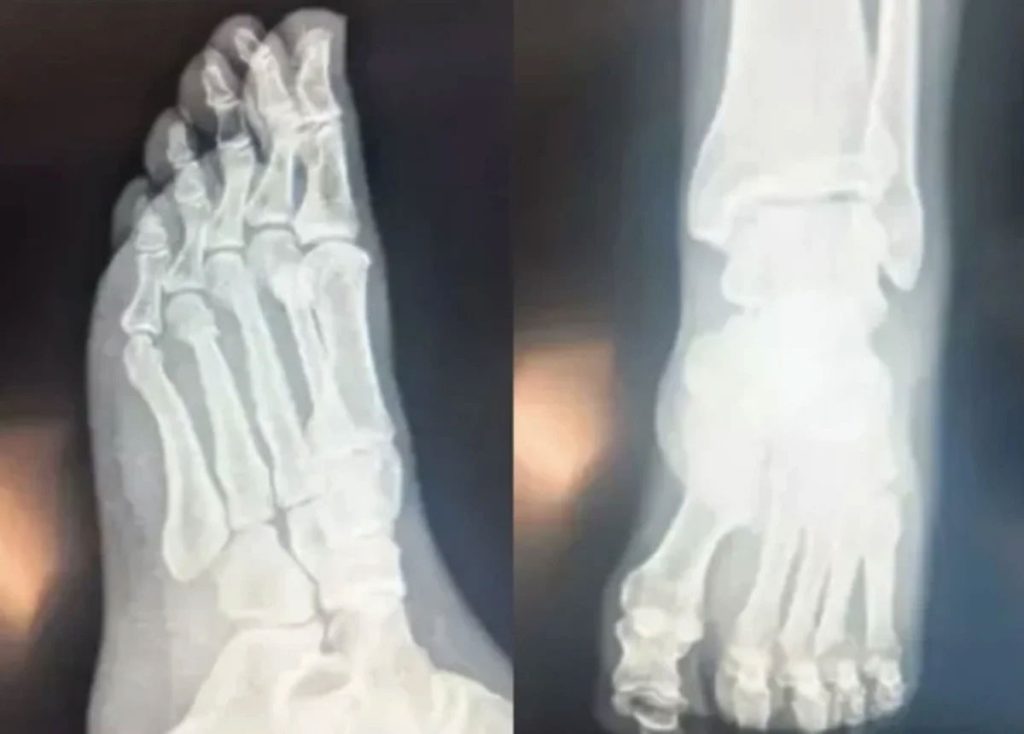

Haberler üzerine açıklama yapan Özel, önceki gün iddialara ilişkin “Bu paylaşımı ilk önce sabah saatlerinde FETÖ’cü hesaplar paylaştı, ben bu paylaşımları görünce FETÖ’cülerin peşinden gidenlerin de bunları paylaştığını gördüm. Benim Güven Hastanesi’nde çekilen filmin e-sağlık üzerinden e-devlet’e yüklüdür. İsteyen bakabilir. Devletin elinde olan filmde parmaktaki kırık ortadadır isteyene filmi de atabilirim’ diye yanıt verdi.

Özel bugün de ayağının çekilen röntgen filmini paylaştı.